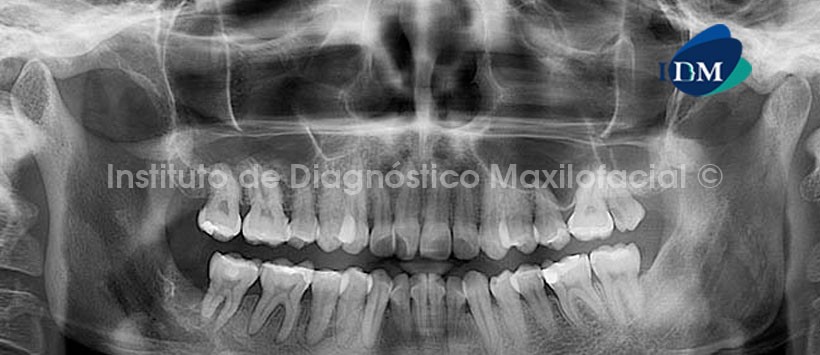

En la radiografía panorámica (Fig. 1) se observa una alteración del patrón trabecular en el lado derecho del maxilar inferior, caracterizado por áreas de rarefacción y de aumento de la densidad ósea  a nivel de las piezas 4.5, 4.6 y 4.7; condicionando el ensanchamiento del espacio periodontal de éstas, y se extiende hacia el reborde alveolar de la pieza 4.8  compromete la zona antegonial, ángulo y rama ascendente.